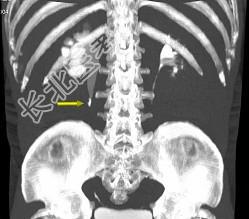

- 多项选择题患者男,36岁, 反复发作的右侧腰背部疼痛伴血尿1年余加重2小时,CT如图所示, 下列说法正确的是 ( )

A、右侧肾盂肾盏扩张

B、右输尿管上段扩张

C、右输尿管内可见沿输尿管走行的高密度影

D、右输尿管结石

E、右输尿管上段钙化